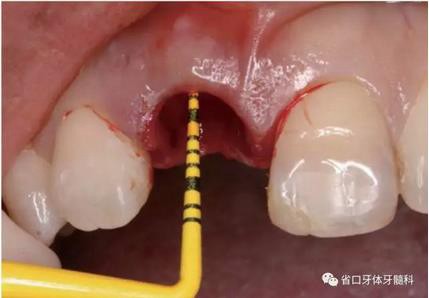

(1)微創(chuàng)拔牙及即刻種植:術(shù)前拍攝口內(nèi)照及實(shí)施牙周基礎(chǔ)治療。常 規(guī)消毒鋪巾阿替卡因局麻下微創(chuàng)拔除上頜右側(cè)中切牙,搔刮拔牙窩及根尖肉 芽組織。探測牙槽骨唇側(cè)骨壁及鄰面牙槽嵴完整,牙齦無撕裂。不翻瓣下于上頜右側(cè)中切牙缺隙近遠(yuǎn)中中點(diǎn)的腭側(cè)牙槽骨及根方定位,按照逐級預(yù)備的原則,緊貼牙槽窩腭側(cè)骨壁制備種植窩洞,植入Zimer®3.7mm×13mm TSV種植體1顆,植入扭矩>35N·cm,以O(shè)sstell測量種植體的ISQ值為68。 種植體平臺(tái)位于唇側(cè)齦緣中點(diǎn)下3mm,與唇側(cè)骨壁內(nèi)側(cè)面形成的跳躍間 隙約2mm,置入Bio-Oss®細(xì)顆粒骨粉0.25g,上愈合基臺(tái)關(guān)閉創(chuàng)口。術(shù)后 CBCT檢查顯示:種植體利用牙槽窩根方骨質(zhì)固位,緊貼牙槽窩腭側(cè)骨壁, 其唇側(cè)面與牙槽窩唇側(cè)骨壁的內(nèi)側(cè)面所形成的跳躍間隙(約2mm)可見顆 粒狀顯影物充填。牙槽窩的唇側(cè)骨壁及唇側(cè)倒凹無缺損穿孔。

圖12 平行桿檢查

圖13 平行桿檢查

圖14 平行桿檢查